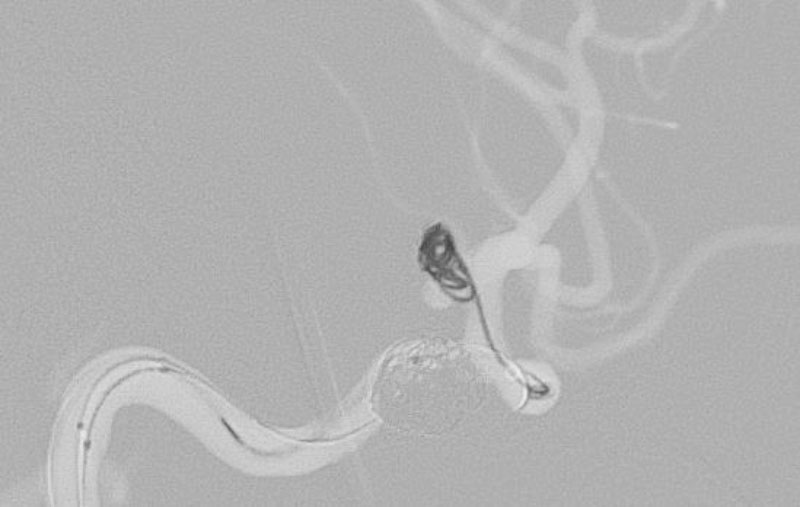

No.1593 手術中

くも膜下出血

右内頚動脈脳動脈瘤破裂

40代

救急外来